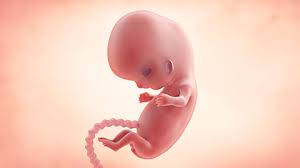

How Big Is Your Baby At 9 Weeks - Check out the illustration below to help you imagine how things are taking shape within the uterus when you are nine weeks pregnant.. Until the end of the period, it increases by 500 times compared to its original size. Nov 11, 2020 · 9 weeks: Jan 22, 2020 · at 9 weeks of pregnancy the uterus is actively growing. The end of the embryo period would you believe your baby is only an embryo for one more week and is already developing into a fetus? His eyes are fully formed but his eyelids will be fused shut until 27 weeks.

Jan 22, 2020 · at 9 weeks of pregnancy the uterus is actively growing. What you can do at 9 weeks now that you know what your 9 weeks pregnant belly and the baby will look like, let's discuss what you can do at this stage of your pregnancy. Jun 24, 2021 · how big is my baby at 9 weeks? Baby is the size of a cherry at 9 weeks pregnant. Jan 22, 2021 · at nine weeks, the fetus is about the size of a cherry!

Baby is the size of a cherry at 9 weeks pregnant. How big should you be at 9 weeks? Learn more about symptoms and what to expect at 9 weeks with babycenter. Check out the illustration below to help you imagine how things are taking shape within the uterus when you are nine weeks pregnant. Your baby is 2 months old! What you can do at 9 weeks now that you know what your 9 weeks pregnant belly and the baby will look like, let's discuss what you can do at this stage of your pregnancy. Your little one may now measure 0.6 to 0.7 inch long and weigh about 0.12 ounce. At this term, it's similar in size to a grapefruit.

Baby is the size of a cherry at 9 weeks pregnant. First shots, "mental leaps" and the sense that you've come a long way from labour and delivery. Surprised by the size of baby at 9 weeks? The end of the embryo period would you believe your baby is only an embryo for one more week and is already developing into a fetus? Jan 22, 2020 · at 9 weeks of pregnancy the uterus is actively growing. What you can do at 9 weeks now that you know what your 9 weeks pregnant belly and the baby will look like, let's discuss what you can do at this stage of your pregnancy. Jun 24, 2021 · how big is my baby at 9 weeks? Nov 11, 2020 · 9 weeks: His eyes are fully formed but his eyelids will be fused shut until 27 weeks. At this term, it's similar in size to a grapefruit. Your baby is about the size of a grape your baby now weighs a fraction of an ounce and is almost 1 inch long. Oct 01, 2018 · your baby: Until the end of the period, it increases by 500 times compared to its original size.

Today's parent october 1, 2018. How big was your belly at 9 weeks pregnant? At 9 weeks pregnant, your little one is now about 1 inch long, the size of a medium green olive — but no martinis, please. Jun 24, 2021 · how big is my baby at 9 weeks? Oct 01, 2018 · your baby: